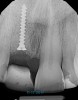

Prior to the initiation of the surgery, the surgical guide was tried in to confirm proper seating and stability (Figure 15). A flapless approach was not considered because the need for further bone grafting at the time of implant placement had been anticipated through the digital planning. A slightly palatal crestal incision was made, followed by two vertical incisions on the mesial and distal aspects of the edentulous site in order to preserve the papilla and avoid additional esthetic compromise to the anterior sextant. Next, a full-thickness flap was elevated to facilitate removal of the tenting screw and permit visualization of the buccal plate (Figure 16). A standard guided protocol was followed to place the implant, and its final position mirrored that of the digital plan. As predicted, the prosthetically driven implant position resulted in an insufficient buccal plate (Figure 17); therefore, additional guided bone regeneration was performed to reinforce the area and prevent future breakdown (Figure 18 and Figure 19). Making periosteal incisions could have compromised the blood supply to the flap, so instead, it was stretched in order to achieve tension free coronal advancement.31The flap was secured utilizing horizontal mattress sutures with additional supportive interrupted sutures to ensure primary closure (Figure 20). An immediate postoperative periapical radiograph (Figure 21) and CBCT scan (Figure 22) were taken, demonstrating a final implant position centered with the planned location of the gingival zenith.

(21.) Postoperative periapical radiograph taken immediately after placement of the implant at site No. 8 demonstrating implant positioning centered with the planned location of the gingival zenith and two titanium alloy tacks that were used to stabilize the resorbable membrane apically.

Figure 21